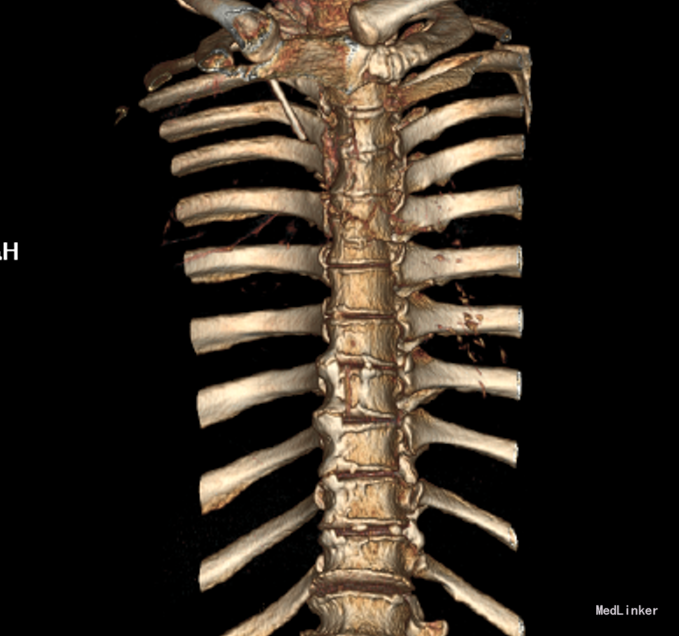

患者于2014-08-13日11:30左右骑摩托车摔倒,伤后一过性意识不清,清醒后感觉胸部疼痛,双下肢活动受限,急诊送至盘锦市宽甸县中心医院,行胸CT、头CT、胸椎三维CT,提示为胸椎骨折,急诊行面部伤口清创缝合,具体治疗不详。患者及家属为求系统治疗,急来我院,急诊予以行辅助检查,提示:胸椎骨折;急诊以“多发外伤”为主诊断收入我科.

诊断:胸3-6椎体骨折,胸髓损伤,双下肢全瘫。 入院后完善检查,查无手术禁忌症后行胸椎骨折后路切开复位椎板减压椎弓根钉内固定术